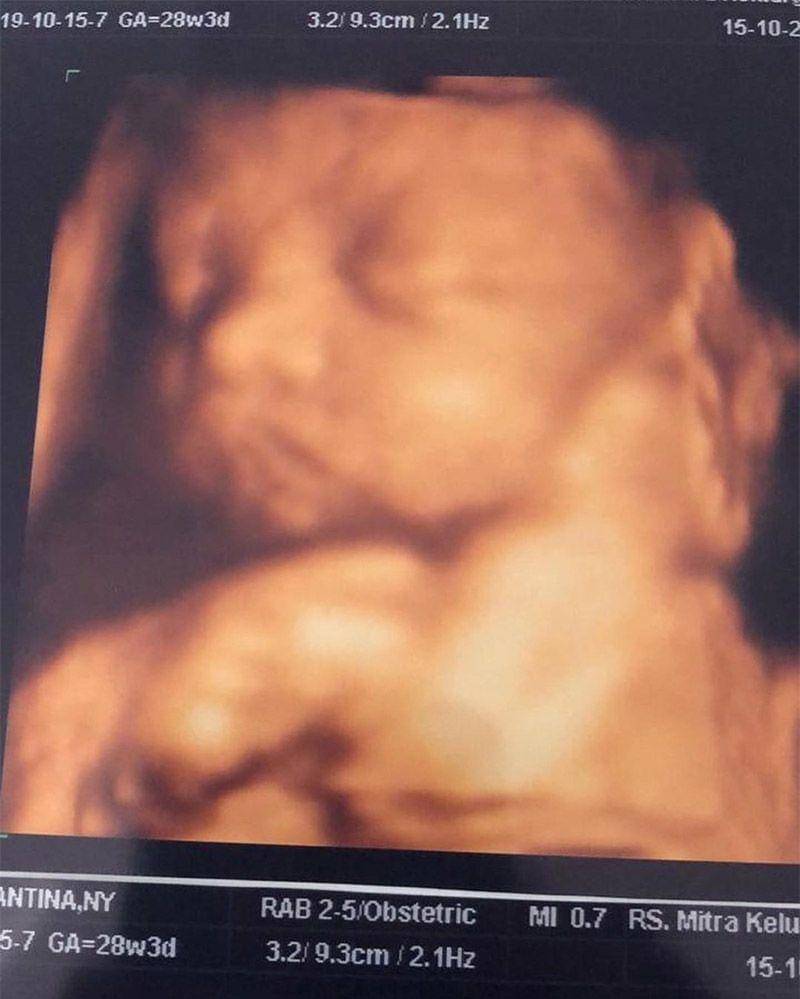

Usai keduanya membagikan banyak kemesraan di media sosial, kini Young Lex dan Eriska kompak untuk mengumumkan kalau calon anak mereka sebentar lagi akan segera lahir. Lewat unggahan foto USG banyak sekali warganet yang kaget sekaligus mengucapkan selamat kepada pasangan ini. Warganet seolah turut bahagia dengan kehamilan Eriska.

Di usia kandungan Eriska yang sudah 28 minggu, maka perlu diketahui kalau ini menjadi awal dari trimester ketiga. Secara umum, berat janin di dalam kandungan ibu hamil di usia 7 bulan sudah bisa mencapai 1.200 gram dengan ukuran sekitar 37 cm dari ujung kepala hingga kaki.

Selama usia kandungan ini, pertambahan berat badan dari anak pertama Eriska dan Young Lex akan signifikan serta jaringan otaknya akan terus mengembangkan lipatan-lipatan pada permukaan yang dulunya masih halus. Lalu beberapa organ dalamnya pun sudah semakin berkembang sempurna seiring usia kehamilan terus berjalan.

Walau ukuran janin bertambah besar, namun tak perlu khawatir karena dirinya masih memiliki ruang bergerak.